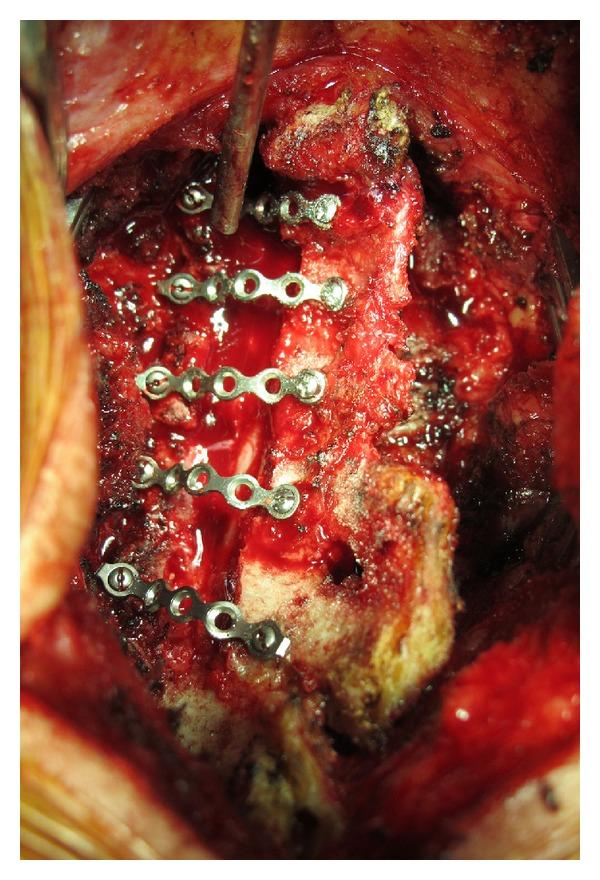

Background. One of the important complications of open-door laminoplasty is a premature laminoplasty closure. In order to prevent premature laminoplasty closure many techniques have been described and a titanium miniplate is one of the instruments to maintain cervical canal expansion. This study was performed to evaluate the effectiveness of titanium miniplates on the union rate for open-door laminoplasty. Materials and Methods. We performed open-door laminoplasty in 68 levels of fourteen patients using maxillofacial titanium miniplates. Axial computed tomography scans were obtained at 6 months postoperatively to evaluate the union rates of the hinge side. The Japanese Orthopedic Association (JOA) score was used to compare the clinical outcomes before and after surgery. Results. Computed tomography scan data was available on 68 levels in 14 patients. There were no premature closures of the hinge or miniplate dislodgements. The union rate on the hinge side was 70.5% (48/68). The mean JOA score increased significantly from 7.0 before surgery to 10.2, 12.2, and 13.0 after surgery at 1, 3, and 6 months, respectively. Conclusion. Open-door laminoplasty using maxillofacial titanium miniplates can provide union rates comparable to other techniques. It can maintain canal expansion without failures, dislodgements, and premature closures.

背景。开门式椎板成形术的重要并发症之一是椎板成形术过早闭合。为了防止椎板成形术过早闭合,人们描述了许多技术,钛微型钢板是维持颈椎管扩张的器械之一。本研究旨在评估钛微型钢板对开门式椎板成形术融合率的有效性。材料与方法。我们使用颌面钛微型钢板对14例患者的68个节段进行了开门式椎板成形术。术后6个月进行轴向计算机断层扫描,以评估铰链侧的融合率。采用日本骨科学会(JOA)评分比较手术前后的临床结果。结果。14例患者的68个节段均获得了计算机断层扫描数据。铰链处无过早闭合或微型钢板移位。铰链侧的融合率为70.5%(48/68)。JOA评分术前平均为7.0,术后1、3和6个月分别显著提高到10.2、12.2和13.0。结论。使用颌面钛微型钢板的开门式椎板成形术可提供与其他技术相当的融合率。它可以维持椎管扩张,而不会出现失败、移位和过早闭合。